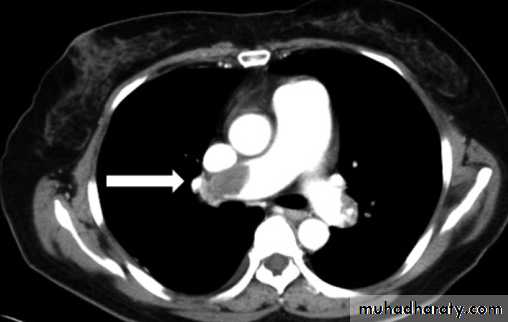

NECT with lt. pulm. A. thrombosis2- Showing shape of intrapulmonary or pleural opacity, detecting calc. or cavitation when plain CXR not conclusive.

7- pulm. embolism.

Pulm. Emb.